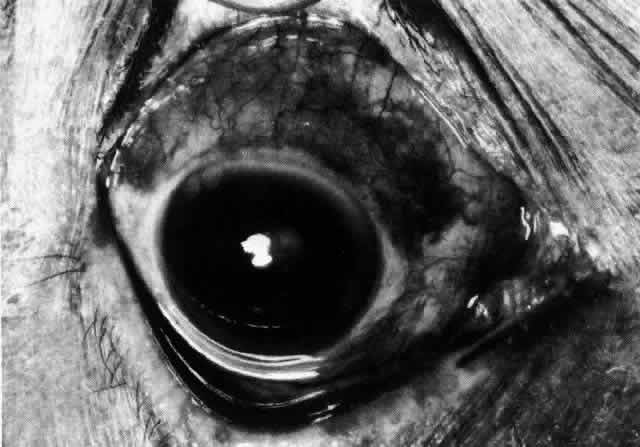

Simple and nodular episcleritis differ in their clinical courses, but in both the edema and infiltration are entirely within the episcleral tissues. The sclera is not involved. The maximum congestion is in the superficial episcleral network, with some slight congestion of the conjunctival vessels and deep episcleral vessels (Fig. 10). The intraocular structures are not involved in either variety, nor is the visual acuity affected. Anterior segment fluorescein angiography reveals a normal vascular pattern but a very rapid flow rate, with the whole transit of the dye being completed within 2 or 3 seconds (Figs. 11 and 12).

Fig. 10. Maximum congestion in the superficial vascular plexus in episcleritis. The conjunctival and deep episcleral networks are separated from the deep plexus by edema and infiltration in the episcleral tissue. (Watson PG, Hayreh S, Awdry P: Episcleritis and scleritis. Br J Ophthalmol 52(3):278–279, 1968)

The redness of simple episcleritis may be intense, varying from a fiery-red or a brick-red discoloration to a mild red flush, but it does not have the bluish tinge that is seen in scleritis. The distribution is usually sectorial but can involve the whole anterior segment of the globe. The episcleral vessels are engorged but retain their normal radial position and architecture (Figs. 13 and 14; Color Plate 1A). In simple episcleritis, there is a diffuse edema of the episcleral tissues. These tissues are sometimes infiltrated with gray deposits that appear yellow in red-free light. Surprisingly, the eye is rarely tender to the touch.

Fig. 13. Infiltration of the episclera in which the superficial episcleral vessels show maximal congestion. Conjunctival vessels are slightly congested, as is the deep episcleral plexus, whose irregular criss-cross pattern can be seen deep to the radially arranged superficial episcleral plexus.